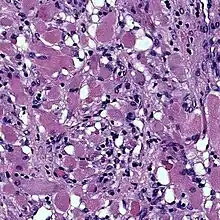

Cardiac rhabdomyomas are the most common primary tumor of the heart in infants and children. It has an association with tuberous sclerosis.[1] In those with tuberous sclerosis, the tumor may regress and disappear completely, or remain consistent in size.[2] A common histological feature is the presence of spider cells, which are cardiac myocytes with enlarged glycogen vacuoles separated by eosinophilic strands, resembling the legs of a spider.